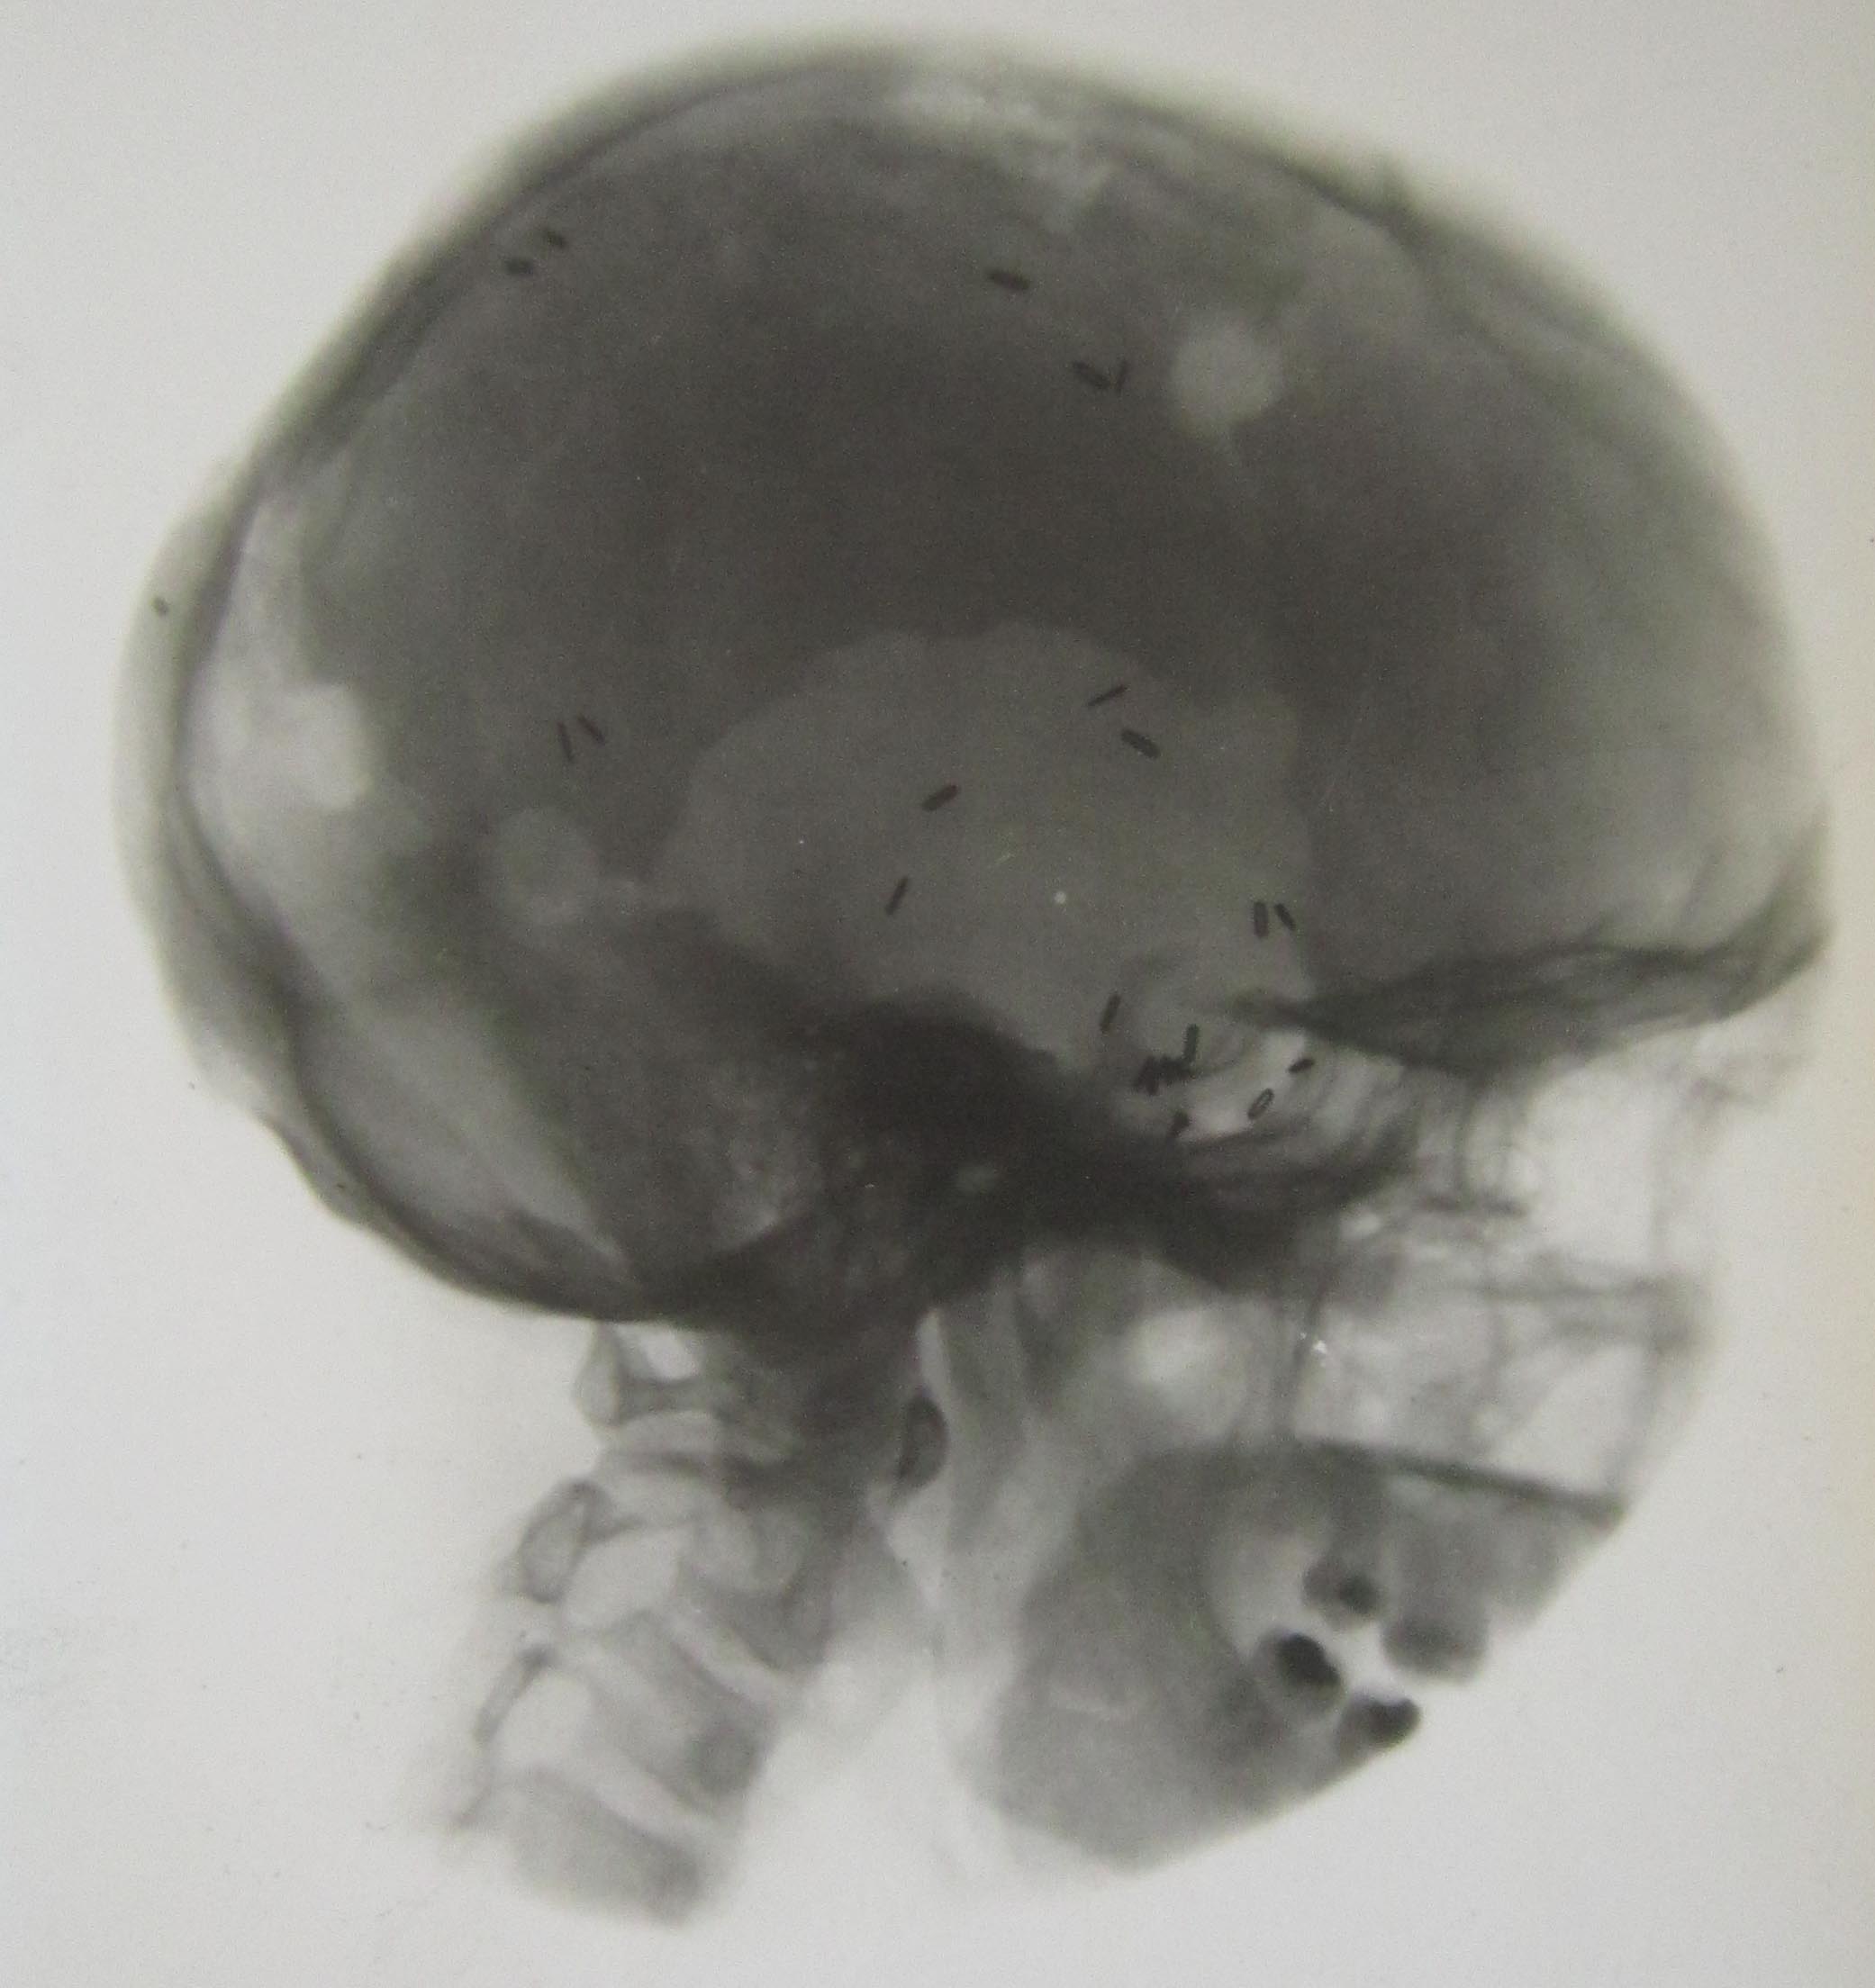

Acknowledgements LHSA gratefully acknowledges the support of the Wellcome Trust. (Please note that personal details have been redacted from the images below.)

September 2015 Clair takes maternity leave - congratulations to Clair and family on the first LHSA baby since 2009! We start recruitment for maternity cover, with interviews in early December. April 2015 Clair starts cataloguing, drawing on the experience she gained of the case note methodology during her internship with us towards the end of 2014. February 2015 We wish Liz all the best for her new job in the historic search room at the National Records of Scotland. There will be a short hiatus until Clair Millar, our Project Cataloguing Archivist for our HIV/AIDS collections, finishes her work on that Wellcome funded project and then moves on to this project. June 2014 Project Cataloguing Archivist, Liz Course, started in post on 19 May and will be covering Louise's period of secondment for the next 12 months cataloguing and promoting the project. She is currently working on cataloguing the largest of the four series of case notes, LHB1 CC/24, Royal Infirmary of Edinburgh, Professor Norman Dott Case Notes, 1941-1959. April 2014 Louise Williams, the Dott Project Archivist, began a 12-month secondment to the LHSA Archivist post on 1 March 2014. Work has continued on the project through the contributions of our volunteers and our 10-week internship, which began in February, but we look forward to appointing a 12-month post to cover Louise's secondment soon. The closing date is 3 April, and we will be interviewing in the week commencing 14 April. October 2013 The first year of the Dott project has been an extremely busy one, not only with the main work of cataloguing patient case records, but also with outreach activities in conferences, seminars, online and published articles and exhibitions. The cataloguing template established with the help of the project’s steering group is adapting well to the sheer variety of documents and situations that Dott’s case notes present. However, after the initial ten-week scoping period of the project, it became clear that it would be extremely difficult to produce a meaningful catalogue entry that would provide a ‘way in’ to the case notes for different groups of researchers inside the original two years allotted to the project. Since it was not possible for us to bid for an initial scoping project to establish cataloguing methodologies prior to the official start date, accurate time-tabling predictions were extremely difficult. In response, LHSA submitted a report to project funders, the Wellcome Trust, detailing various proposals for the future, and we are glad to say that our preferred solution (providing additional funding with a provision for volunteer help) was accepted. As a result, the project will continue until June 2015. Not only has the additional time allowed us to produce a valuable catalogue entry for every record within our Dott case note collections, but also the aid of volunteers has changed the landscape of the project considerably. Since March 2013, four volunteers have contributed valuable additional catalogue entries to the project. Not only do volunteers quicken progress, their help also means that the project cataloguing method (without precedence in UK medical archives) is passed on to new groups of people interested in careers in archives. Cataloguing using Encoded Archival Description (EAD) is also a valuable, practical skill in a competitive job market that is focusing more and more on abilities to deliver digital research resources. Most importantly, having volunteer involvement in the Dott project has made a solo cataloguing effort into a team one. March 2013 On Thursday 7 March, Louise attended the UK Archives Discovery (UKAD) Forum held at the National Archives, Kew. Together with Clare Button, Archivist for the 'Towards Dolly' project (cataloguing materials related to the development of animal genetics in Edinburgh), Louise presented a poster on the way in which the CRC has been working to open up history of science records to new researchers thanks to funding from the Wellcome Trust. During the poster session, Louise and Clare answered questions related to their projects and made valuable connections with archivists around the country working with similar records and sharing similar objectives. The UKAD Forum is a chance to hear current thinking on the different ways in which archives can reach new and current audiences through information technology and to discuss the challenges of maintaining born-digital and digitised records. The popularity of the day proved that making archive catalogues available and accessible, promoting collections online and securing the future of digital holdings are essential aspects of the archivist’s role in the twenty-first century. The poster produced for the forum is available here, and also in a summary flyer here. Useful Links: Towards Dolly: http://towardsdolly.wordpress.com/ UKAD Forum 2013: http://www.ukad.org/forum2013/ December 2012 Starting in September 2012, the first stage of the project has concentrated on research into Dott’s patient case note records and the development of ideas for the structure of an online catalogue. Since case notes left by Dott describe over 26,650 individual patients inside four record series, it was essential to review a significant sample of the records. There are few (if any) precedents for item level catalogues for modern case note records – a period of this initial stage was spent in deciding upon the design and content of the Dott catalogue and putting measures in place to protect the personal data of individual patients in that catalogue (more information about legislation covering medical records can be found here). Scoping The case notes held by LHSA document the majority of Dott’s professional career, from private practice and surgery in nursing homes to his time in Ward 20 of the Royal Infirmary of Edinburgh (which became the first Department of Surgical Neurology in Scotland, opening in 1938) and his Second World War service in Bangour General Emergency Medical Service Hospital. Not only do these series cover the significant advances made by Dott in operative and rehabilitative treatment of neurological conditions, but they contain a great variety of written and image records, including typed case summaries, letters, charts, reports, photographs, x-rays and glass plate negatives. In looking at these different records, it was clear that there is no ‘typical’ patient case note, that information about patients is conveyed in many different ways and in varying levels of detail, and that decisions and diagnoses are not always clear-cut. Catalogue design An online catalogue will be produced as a result of the project, allowing researchers to search the case notes based on key criteria such as patient age at first treatment, sex and medical condition. To enable this level of functionality, the catalogue will be designed using Encoded Archival Description (EAD). EAD is a standard that reflects archive hierarchies and is written in eXtensible Mark-up Language (XML) - a language that structures and labels text for online display. Using EAD allows the linking of catalogues both within and across archive collections, benefitting researchers and the archive community at large. In this first stage of the project, the Project Archivist has identified key information that will be labelled using EAD to allow users to perform advanced catalogue searches, and has researched the manner in which these extremely specialist records can be described and indexed effectively and accurately – no easy task across such varied collections! The next stage A Project Steering Group comprising archive professionals, an academic specialist in medical history and a retired Consultant Neurologist met on 5 November 2012. After time looking at some case notes, the group discussed how a catalogue can be of most use to historical and clinical researchers, approved the essential information that will be described within it, and agreed upon priorities for cataloguing. The main cataloguing stage of the project has now begun, taking a step further in making these valuable resources accessible to researchers both online and in the search room. August 2012 We have recruited the Project Archivist, Louise Williams, and the project will start on 1 September. Our new recruit's first day will be Monday 3 September. June 2012 The deadline for applications for the two-year, fixed-term Project Archivist post has now passed and the recruitment process is well underway.